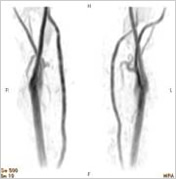

頸動脈MRA画像

左頸部頸動脈に

狭窄を認める